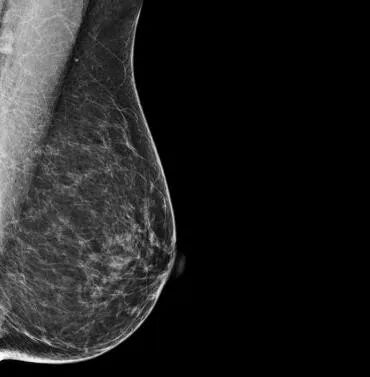

乳腺X线(钼靶):未见恶性肿瘤征象(图1)。

图1:乳腺X线